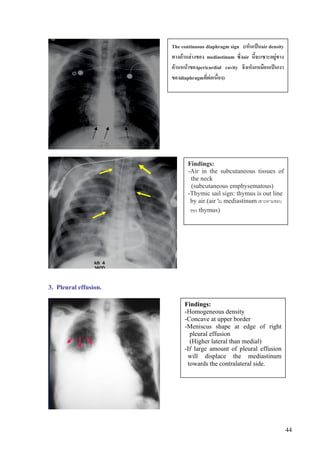

The continuous diaphragm sign (เห็นเปนair density

ทางดานลางของ mediastinum ซึ่งair นี้จะเซาะอยูทาง

ดานหนาของpericardial cavity จึงเห็นเหมือนเปนเงา

ของdiaphragmที่ตอเนื่อง)

Findings:

-Air in the subcutaneous tissues of

the neck

(subcutaneous emphysematous)

-Thymic sail sign: thymus is out line

by air.(air ใน mediastinum เซาะตามขอบ

ของ thymus)